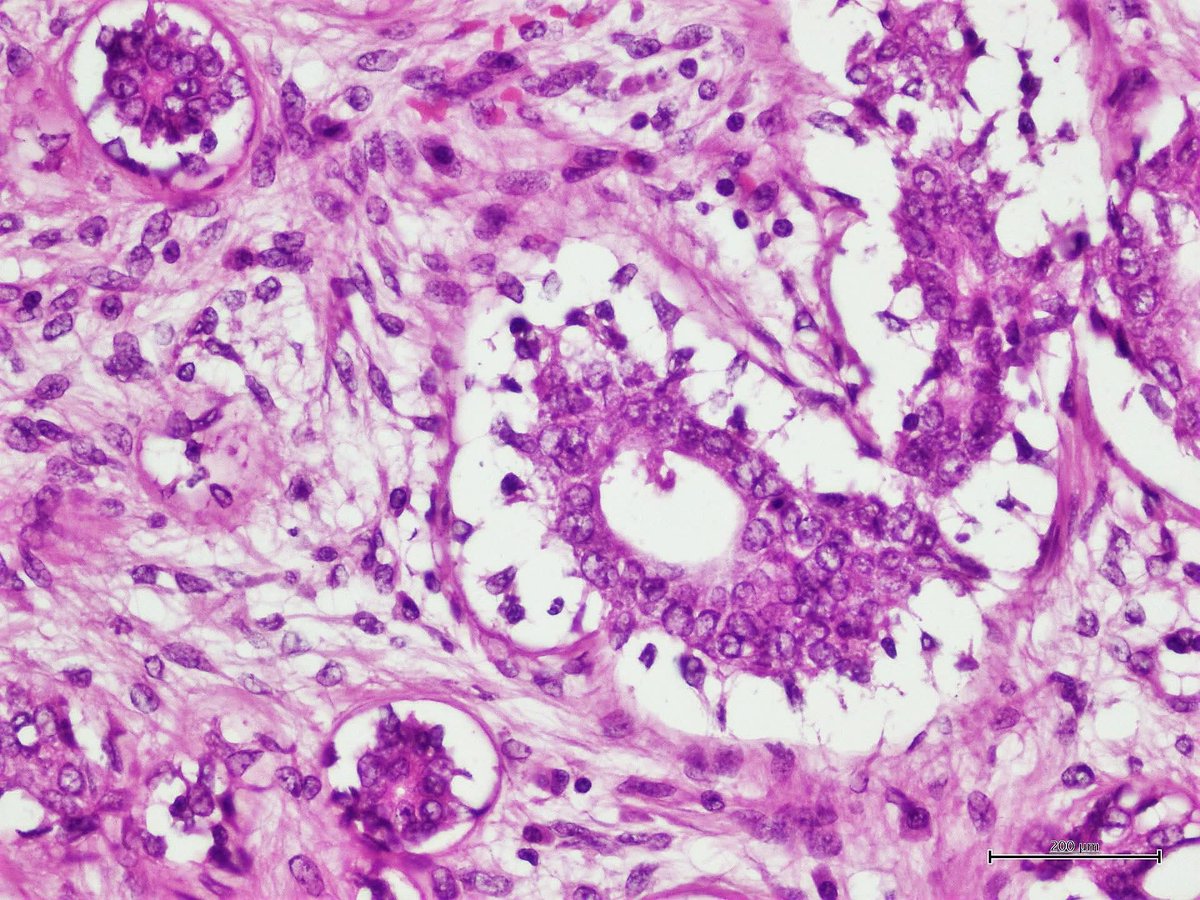

A nasty cervical lymph node metastasis of ovarian serous carcinoma with micropapillary growth pattern. This poor lady has clinically advanced MOT with pulmonary nodules and cervical lymphadenopathy. #pathology #Gynaepath #Oncopath